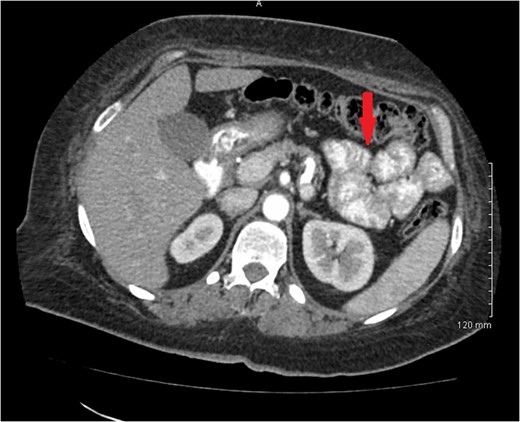

1). There was no evidence of metastatic disease. A 3.8 × 3.3 cm hypodense mass located in the central portion of the uterus was also noted (Fig.

2).

Figure 2:

CT scan of pelvis showing uterine hypodense mass.